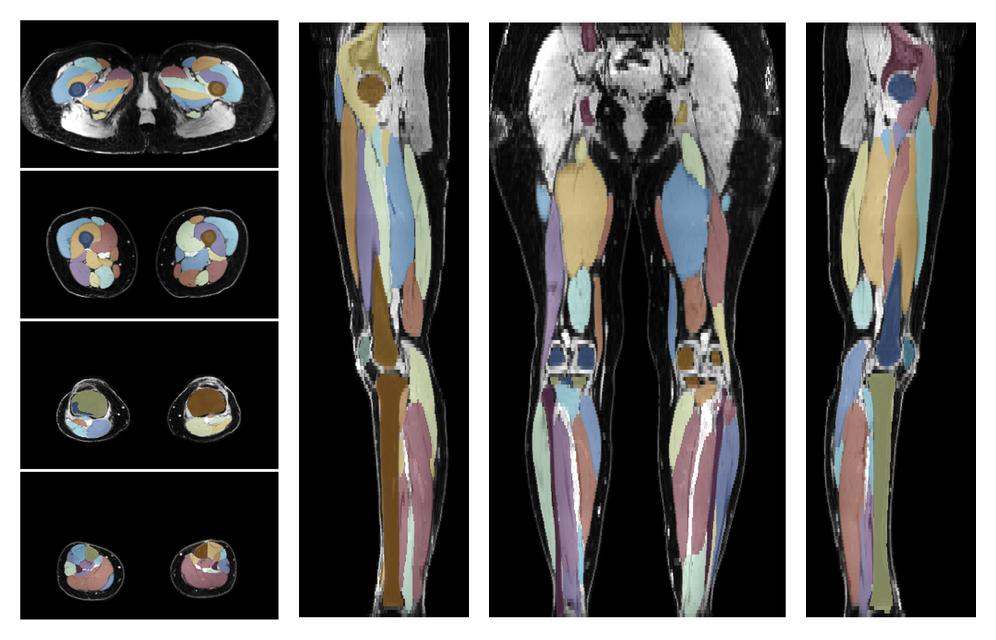

• Automated muscle and bone segmentation.

Overlay of automated muscle segmentation labels on dixon water image.